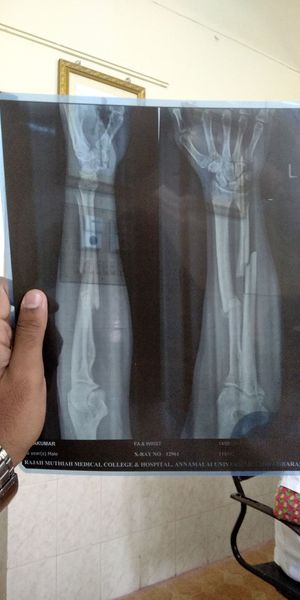

Compound fracture due to outstretched fall

Xray

Orthopaedics

Fractures